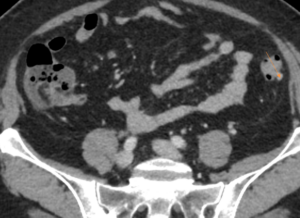

TC abdominopélvico (corte axial)

Hallazgos radiológicos: